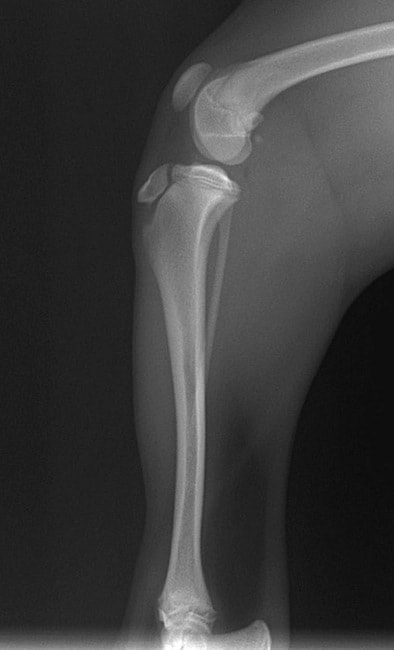

■ 症例22 ポメラニアン 1歳5か月 去勢雄

左後肢の挙上を主訴に来院した。整形学的検査、レントゲン検査より左右の膝蓋骨脱臼(左GradeⅡ〜Ⅲ、右Grade Ⅱ)を認めた。また、脛骨の前方引き出し試験の際に、引き出し兆候は認められないものの、疼痛が認められたため、前十字靭帯の損傷が疑われた。術中における、目視および関節内の操作によって、前十字靭帯の損傷や過伸展といった異常が認められなかったため、膝蓋骨脱臼の整復のみ実施した。手術手技は縫工筋及び内側広筋の解放、脛骨粗面の外側転位、滑車ブロック形造溝術、内外側関節包の縫縮を実施した。本症例は跛行もなく経過良好である。しかし、頸骨高平部の角度(TPA)が 右26.2°、左24.9°であり、解剖学的に前十字靭帯損傷のリスクが高いことから今後の経過に注意が必要である。